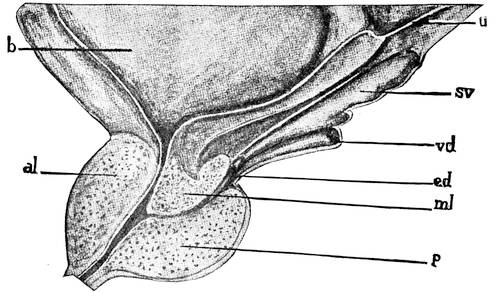

The male genitals, scrotum, testicles, descent of testicles, vas deferens, spermatic cord, seminal vesicles, ductus ejaculatorii, urethra, prostate, colliculus, sinus pocularis, penis.

Vas deferens.—The vas deferens runs down the posterior wall of the epididymis and turns upwards to enter the abdominal cavity through the inguinal canal. It then runs between bladder and rectum to end as the ductus ejaculatorius. Before the vas deferens receives the duct of the seminal vesicle it forms a spindle-like enlargement, the so-called ampulla. The vas deferens opens under the name of ductus ejaculatorius into the prostatic urethra.

The length of the vas deferens is about 60 centimeters, its diameter is about 3 millimeters. The wall of the vas deferens is very thick, giving on palpation the feeling of a piece of rope. It is lined inside with a light cylindrical epithelium which rests upon a layer of fibrous connective tissue. This fibrous substratum is surrounded by a thick, muscular coat of non-striated fibres. The muscular coat is composed of two longitudinal layers, which include between them a circular layer. The muscular coat is surrounded by a layer of connective tissue, the so-called adventitia.

Spermatic cord.—In its course from the testicle to the internal ring of the inguinal canal the vas deferens is accompanied by the arteria and vena spermaticae internae. The three organs form the spermatic cord. But although the three organs are intimately connected, still the vas deferens is recognizable without difficulty by its rope-like consistency and is easily severed, as in the operation for the sterilization of the male. The vein forms a tendril-like tress-work, which is called the plexus pampiniformis. In pathological conditions the plexus forms the varicocele.

Seminal vesicles.—The seminal vesicles may be considered as diverticles of the vasa deferentia. The vesicles are lying in the sulcus, between the prostate and the bladder, and extend oblique33ly outward and backward. The length of the seminal vesicles is about 8 centimeters, their diameter is about 7 millimeters. The vesicles form a bulbous mass of convoluted tubes. Being a derivative from the vas deferens, the wall of the tubes consists of the same strata as the vas deferens, i. e., of an adventitia followed by the muscular coat, then by the fibrous substratum, and finally by a layer of cylindrical epithelia. The mucous membrane possesses numerous tubulous glands. In this way the vesicles serve not only as reservoirs for the sperma, but may be considered as veritable glands. By the junction of the pointed ends of the seminal vesicles with the vasa deferentia, the ejaculatory ducts are formed.

Ductus ejaculatorii.—The ejaculatory ducts traverse the prostate and open, by slit-like orifices, into the sinus pocularis. The wall of the ducts is much thinner than that of the vas deferens. The muscular fibres of the latter are gradually substituted in the ducts by cavernous tissue. The mucous membrane differs little from that of the vas deferens and of the seminal vesicles.

Urethra.—The urethra is divided into three parts, the pros34tatic, the membranous and the cavernous parts. The prostatic part is the widest portion of the entire urethra. It is surrounded by an unstriped muscular layer and the muscles of the prostate. The membranous part is the narrowest, shortest, and most thin-walled portion of the three parts of the urethra. It is entirely surrounded by the muscular fibres of the diaphragma urogenitale, which takes here a circulatory course. It is in this way situated35 on the border-line of the abdominal cavity and the exterior, within the abdominal wall. The cavernous portion of the urethra is surrounded by the corpus cavernosum urethrae. This portion shows two dilatations, one in the bulbous part, just anterior to the termination of the membranous part, where the ducts of the two Cowper’s glands open; the other dilatation is near the end, behind the meatus, forming the so-called fossa navicularis. The meatus itself is the narrowest part of the entire urethra. Numerous mucous crypts, the glands of Littré and certain lacunae, the largest among them near the fossa, open into the lumen of this part of the urethra. The entire urethra is lined with a cylindrical epithelium, except at the fossa navicularis. The latter is covered by a layer of pavement epithelia. The length of the urethra is about 18 centimeters. In the usual state the urethra possesses only a virtual lumen, i. e., the walls touch each other.